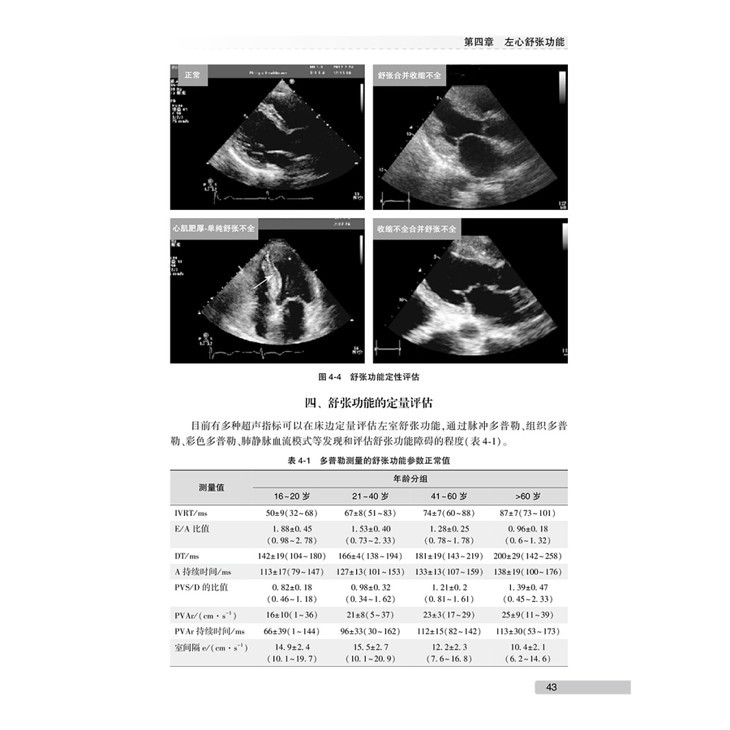

第四章 左心舒张功能/ 40